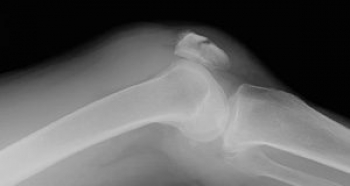

膝蓋骨とは

膝関節の前面にある扁平な骨です。

種子骨のうち最大のもので、俗に「ひざのお皿」といわれます。

上端には大腿四頭筋がつき、下端には脛骨前面上部との間に膝蓋靭帯があり、

膝を動かしたり、保護する役割を果してます。

膝蓋骨骨折

膝蓋骨は、膝の前面にあるため、膝関節の保護と膝の伸展の働きを手助けします。

皮膚直下にあるため、損傷しやすく、骨折の多くは横骨折で腱の断裂、骨片の離開を認められ手術になります。